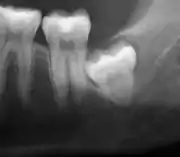

Asymptomatic disease-free impacted wisdom teeth in 21-year-old

The Cochrane review of surgical removal versus retention of asymptomatic disease-free impacted wisdom teeth suggests that the presence of asymptomatic impacted wisdom teeth may be associated with increased risk of periodontal disease affecting adjacent 2nd molar (measured by distal probing depth > 4 mm on that tooth) in the long term. Few studies, however, met the criteria to be included in the Cochrane review and those that were included provided very low quality evidence and had a high risk of bias. Another study which was at high risk of bias, found no evidence to suggest that removal of asymptomatic disease-free impacted wisdom teeth has an effect on crowding in the dental arch. There is also insufficient evidence to highlight a difference in risk of decay with or without impacted wisdom teeth.[17]

Due to the lack of sufficient evidence to determine whether such teeth should be removed or not, the patient's preference and values should be taken into account with clinical expertise exercised and careful consideration of risks and benefits to determine treatment.[28] If it is decided to retain asymptomatic disease-free impacted wisdom teeth, clinical assessment at regular intervals is advisable to prevent undesirable outcomes (pericoronitis, root resorption, cyst formation, tumour formation, inflammation/infection).[17]